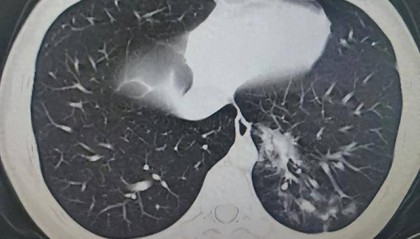

14岁男生4天高烧不退!一查不是甲流,竟是这种感染

冬季寒潮来临,呼吸道疾病进入高发期,中疾控报告显示:流感病毒阳性率“跃居第一”。 14岁的初中生昊昊...